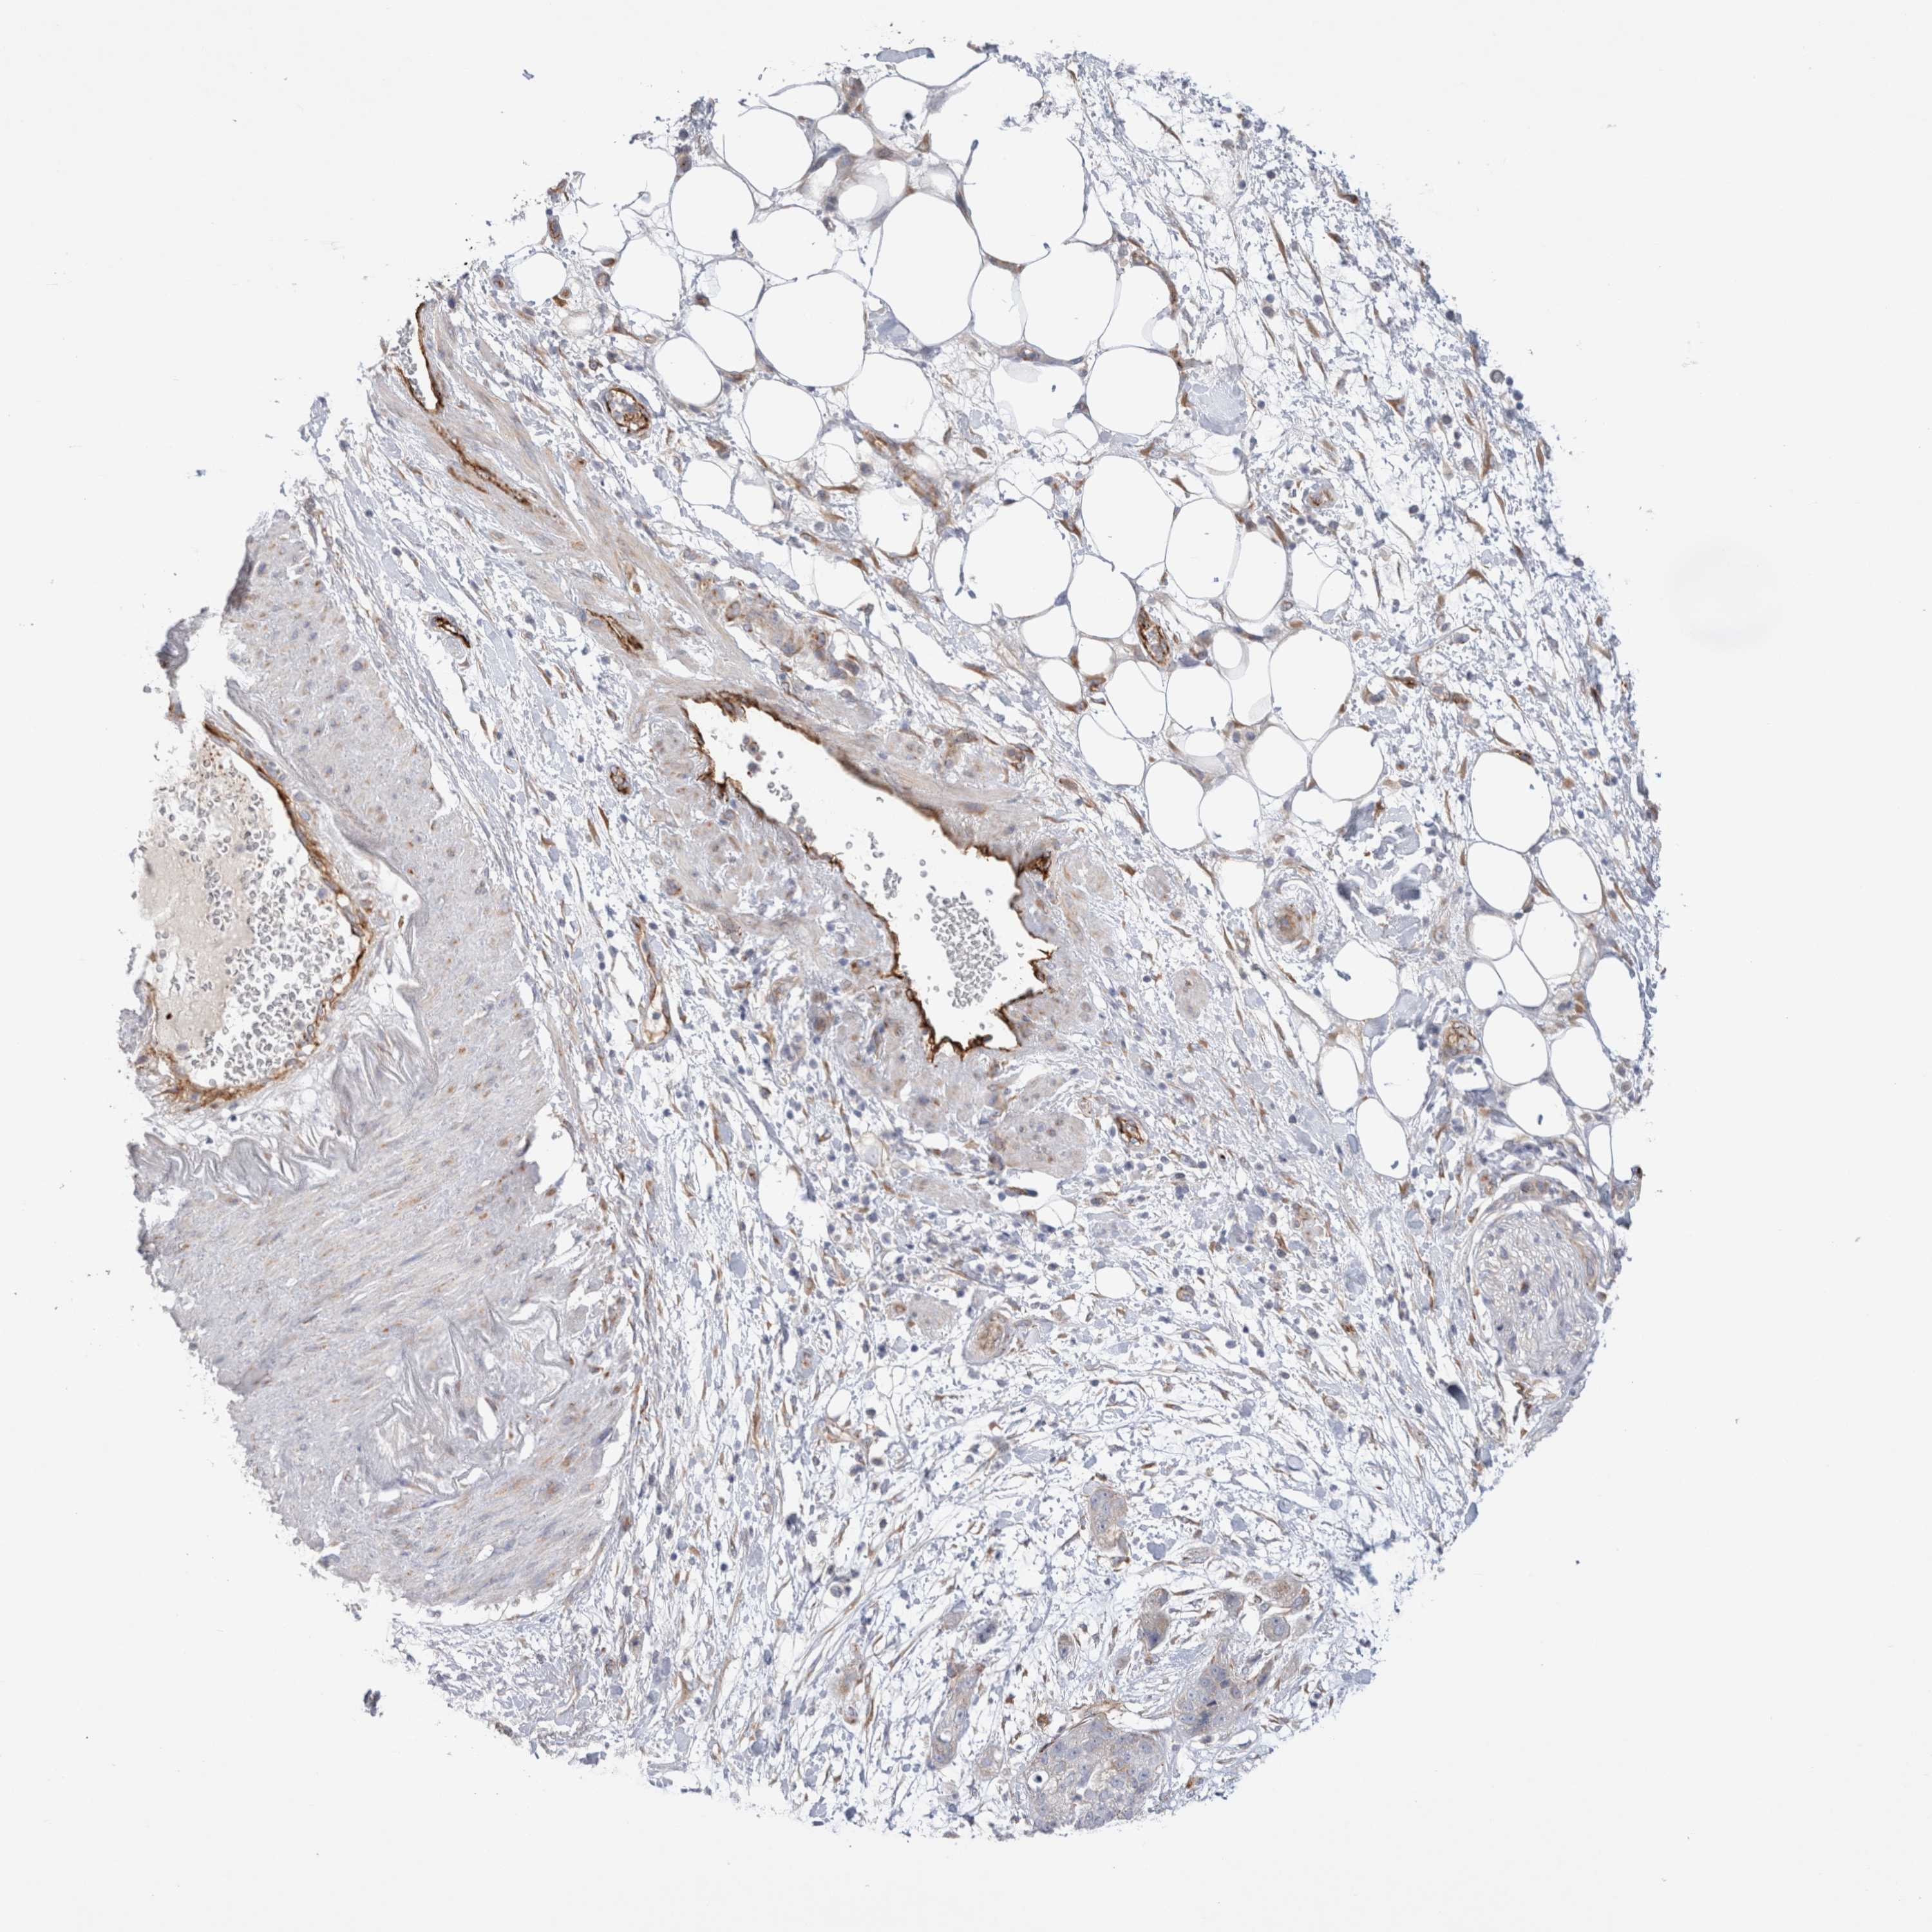

PANCREATIC CANCER - Protein expressioni

A mouse-over function shows sample information and annotation data. Click on an image to view it in a full screen mode. Samples can be filtered based on level of antibody staining by selecting one or several of the following categories: high, medium, low and not detected. The assay and annotation is described here.

Note that samples used for immunohistochemistry by the Human Protein Atlas do not correspond to samples in the TCGA dataset.

Antibody stainingi

Antibody staining in the annotated cell types in the current human tissue is reported as not detected, low, medium, or high, based on conventional immunohistochemistry profiling in selected tissues. This score is based on the combination of the staining intensity and fraction of stained cells.

Each image is clickable and will lead to virtual microscopy that enables deeper exploration of all samples and also displays staining intensity scores, fraction scores and subcellular localization as well as patient and tissue information for each sample.

Antibody HPA014166

Antibody HPA025240

Staining

High

Medium

Low

Not detected

Intensity

Strong

Moderate

Weak

Negative

Quantity

>75%

75%-25%

<25%

None

Location

Nuclear

Cytoplasmic/membranous

Cytoplasmic/membranous,nuclear

Adenocarcinoma, NOS

Adenocarcinoma, metastatic, NOS